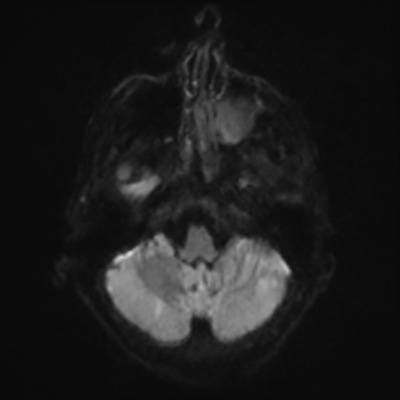

MRI brain (DWI)

You can clearly see diffuse cortical and basal ganglia diffusion restriction, and that of his deep cerebellar nuclei as well. The right occipital lobe abnormalities are a little more prominent, but then you remember that he is known to have had a right occipital stroke weeks ago.